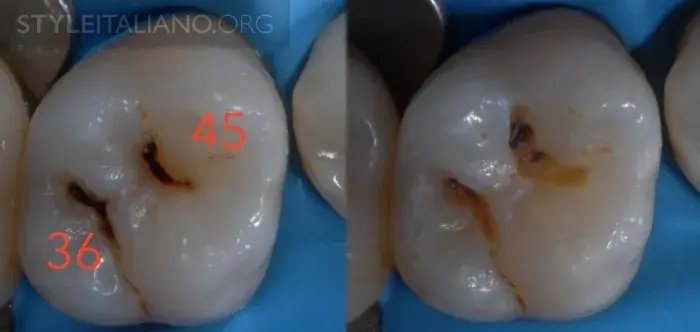

Рис. 9 – Предварительная рентгенограмма. Скрытый кариес: кариес дентина на окклюзионной поверхности. Деминерализация достаточно большая, чтобы обнаружить ее с помощью просвечивания.

Рис. 10 — Раскрытие полости.

Рис. 11- Раскрытие полости.

Рис. 12 – Восстановление зуба.

Рис. 13 — Можно использовать специальный лазер (Diagnodent Pen) для диагностики фиссуры: если цифра больше чем 25, значит есть кариозный процесс.

Рис. 14 – Лечение кариеса.

Рис. 15 — Предоперационный вид/ Лазерное просвечивание/ Рентген.